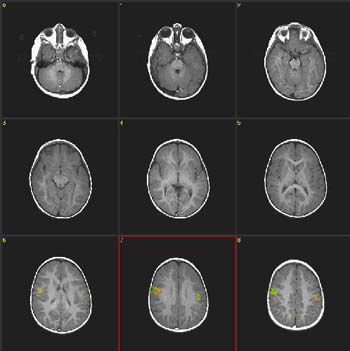

| Caso 1 |

Niña de 2 meses de edad con hidrocefalia |

ACTIVADO: Presentación de la voz de la madre, pregrabada, en la que usa palabras familiares

DESACTIVADO: Nada. Paciente sedado con hidrato de cloral |

0,0007 |

3,4 |

| Activación |

Se observa activación bilateral de las circunvoluciones precentrales y la circunvolución temporal superior derecha. La activación de la corteza motora ocurre en el nivel de la representación oral-facial. Se supone que esto está relacionado con el acostumbramiento-desacostumbramiento a la succión de amplitud alta en respuesta a estímulos lingüísticos. Esta respuesta es de gran importancia en la preservación de nuestra especie. |